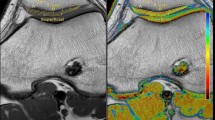

Trochlear dysplasia as a risk factor for progressive knee joint degeneration. Column A: Patient with normal trochlear configuration and without morphological cartilage defects at baseline and at follow-up after MPFL reconstruction. Column B: Patient with trochlear dysplasia and with no patellar cartilage defect at baseline but with new patellar morphological cartilage loss at follow-up after MPFL reconstruction. All images are transverse intermediate weighted turbo spin echo sequences with fat saturation

T1rho (upper row) and T2 (lower row) color maps of the patellar cartilage overlaid on the first-echo images. Blue color indicates low and red color high cartilage relaxation times. Subjects with normal preoperative patellar tilt and normal TTTG distance (column A) showed lower cartilage relaxation times than subjects with high preoperative patellar tilt and high TTTG distance (column B)